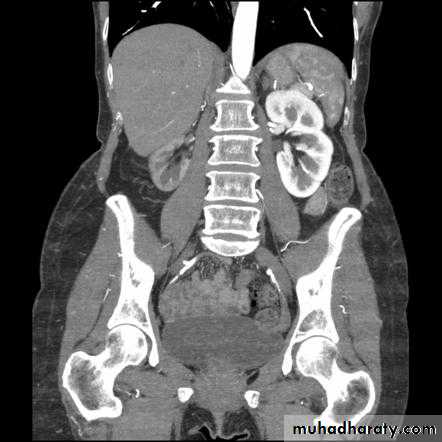

Renal artery stenosis “Multiphase CT of the renal tract demonstrates an atrophic right kidney with a delayed nephrogram, with only the tip of the upper pole enhancing